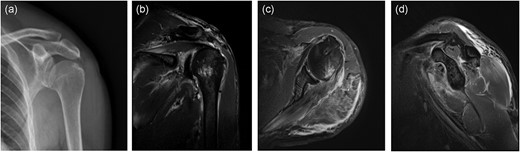

We performed arthroscopic repair of left shoulder under anesthesia on 20 November. We first used three 2.9 mm anchors to repair the bony bankart injury. Then the subacromial bursa was cleaned and the acromioplasty was performed, the coracoacromial arch was preserved, and a 4.5 mm anchor was used to repair the subacromial tendon in the footprint area of the rotator cuff. Finally, in the Chinese-Way technique, a 4.5 mm anchor was used to move the biceps tendon backward, and supraspinatus and infraspinatus tendons were sutured laterally to the long head of the biceps tendon, respectively, the anterior and posterior supraspinatus tendons and the lateral infraspinatus tendons were fixed with 4.5 mm anchors. Postoperative X-ray and MRI revealed the left humeral head returned to its anatomic position, the rotator cuff tear, and the bony bankart injury had been repaired (Fig. 3a–d).

Postoperative imaging: (a) anteroposterior X-ray of the left shoulder; (b) anteroposterior MRI of the left shoulder; (c) coronal MRI of the left shoulder; (d) sagittal MRI of the left shoulder.